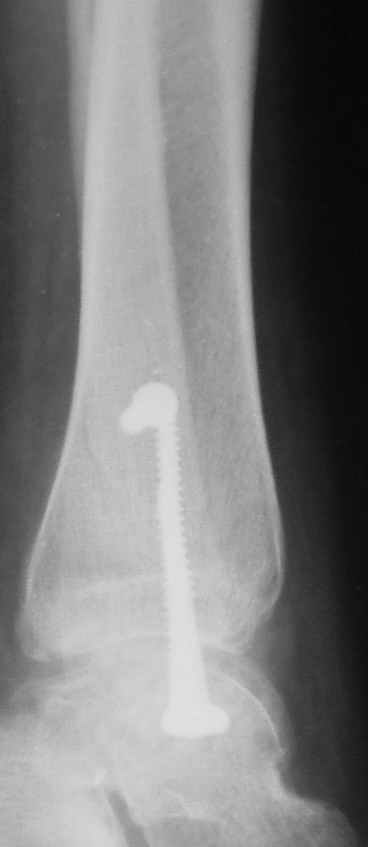

Через месяц

|

Боковой через месяц

Риторический вопрос - в каком руководстве рекомендован такой способ остеосинтеза наружной лодыжки?

Очевидно, такой результат операции был запрограммирован. При невосстановленной длине и практически нефиксированной малоберцовой кости (этот кортикальный винт - как карандаш в стакане), при неустраненном подвывихе, невправленной и тоже нефиксированной внутренней лодыжке нет стабильной вилки сустава. Если такую операцию сделать даже сразу, а не через 4 месяца, то результат ожидаем

тот же.

Вариант с артродезом уже обсудили. Хотя, после увиденых снимков, пессимизм насчет восстановительной операции у меня, например, несколько уменьшился. Особенного уж какого-то остеопороза не видно даже на январских снимках. Можно черед мини-доступы убрать винты, аппаратом вправить малоберцовую кость, устранить подвывих стопы. Ну а дальше фиксировать малоберцовую пластиной сзади. А может, и напряженной Y-спицей попробовать - Анатолий Федорович, как Вы полагаете? Внутреннюю - то, что осталось, если уже не получится сделать спицами и проволокой, то что-то типа пластики дельтовидной связки. А может, и не трогать ее вовсе... В общем, выбор непростой,

много факторов надо взвесить.